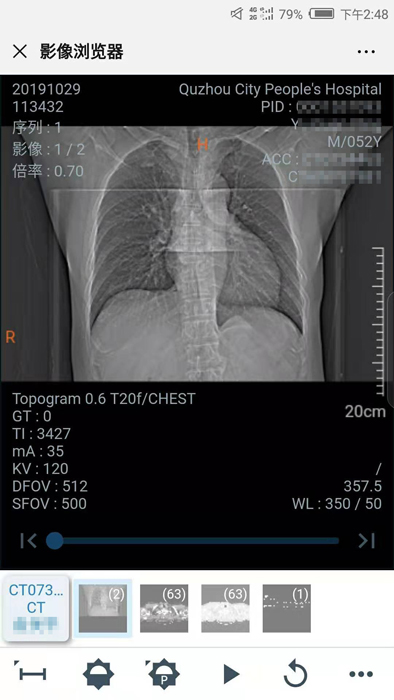

10月29日晚,我院向住院患者推行數(shù)字影像服務(wù),云膠片正式上線!點(diǎn)點(diǎn)手機(jī)就能查看片子不限次數(shù)瀏覽影像……方便、省錢、精準(zhǔn)、環(huán)保,“云影像”服務(wù)平臺(tái)讓您看病更省心。

10月30日,住院患者俞先生收到一條短信提醒“【云影像】衢州市人民醫(yī)院提醒您,俞先生的CT報(bào)告已完成……”俞先生隨即點(diǎn)擊手機(jī)上的瀏覽鏈接,輸入身份證后六位,驗(yàn)證完成,短短幾秒鐘,躺在病床上也能查看到自己的CT電子報(bào)告和影像,俞先生直呼神奇。

“醫(yī)院面向住院患者全面推行檢查檢驗(yàn)結(jié)果電子化,互認(rèn)共享,全面提供網(wǎng)上查詢、移動(dòng)推送等服務(wù),‘云影像’平臺(tái)的運(yùn)行就是深化‘最多跑一次’改革要求的又一新舉措?!贬t(yī)院信息處工作人員介紹,“ ‘云影像’是儲(chǔ)存在云端的病人醫(yī)學(xué)影像檢查信息,包括檢查報(bào)告、電子膠片及供專業(yè)影像科醫(yī)生診斷瀏覽的全部醫(yī)學(xué)數(shù)字原始影像。放射檢查報(bào)告完成后,醫(yī)院會(huì)同步發(fā)送提醒短信到患者的手機(jī)上,只要點(diǎn)擊短信上的鏈接就可第一時(shí)間獲取‘云影像’及報(bào)告。使用‘云影像’查看檢查報(bào)告,解決了排隊(duì)取片、復(fù)診帶片的煩惱,縮短了就醫(yī)時(shí)間,讓老百姓看病得到實(shí)實(shí)在在的方便?!?